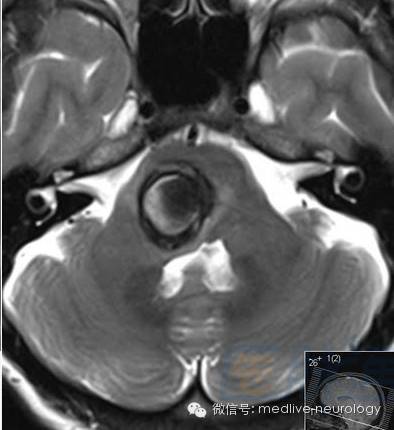

然后解决第三个问题,轻松一下,图来啦,让我们巩固一下今天学习的成果,均为先T1,后T2。

慢性期(>14d):箭头